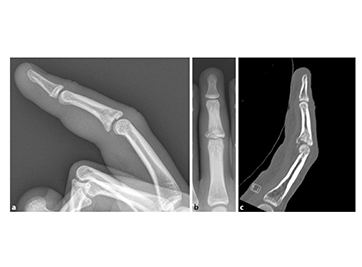

Наконец, с помощью рентгеноскопии проверяли стабильность проксимального межфалангового сустава (ПМФ) в положении 0°. Соединение PIP должно оставаться стабильным в диапазоне от 20° до 90°. Если сустав PIP все еще имеет тенденцию к подвывиху, необходимо ввести стальной штифт от отведения в костномозговой канал или использовать динамический дистракционный фиксатор (c, d).